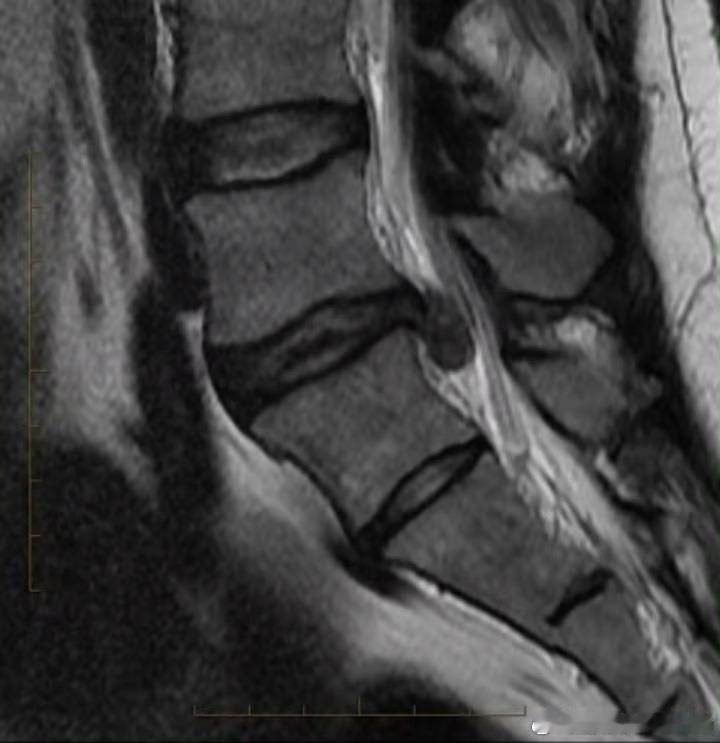

腰椎间盘突出 【腰突康复】继续来聊聊腰突,从基本的概念➕康复黄金法则➕康复误区:01.【椎间盘到底是什么】想象我们的脊椎骨像汉堡一样叠在一起,椎间盘就是中间的"缓冲垫"。它由两部分组成:✅外层纤维环:类似轮胎的坚韧结构✅内部髓核:类似果冻的凝胶物质当纤维环破裂导致髓核外流,压迫后方神经时,就会引发各种症状。02.【典型症状辨别】椎体中央刺痛:按压脊椎间隙时出现针扎样疼痛放射性窜麻:从臀部到脚底有过电般的放电感钝性疼痛:常见于小腿外侧/大腿内侧/臀部,易被误诊为肌肉损伤⚠️注意:单纯腰两侧或腰骶部疼痛,更可能是腰肌劳损、筋膜炎等问题03.【致病原因】椎间盘能承受600kg垂直压力,真正怕的是"剪切力":❌弯腰搬重物❌瘫坐姿势❌久坐不动的办公族❌髋关节灵活性差会加重腰椎代偿,增加发病风险04.【病情发展三阶段】膨出:纤维环未破裂(可逆)突出:纤维环部分破裂脱出:髓核完全流出(不可逆)提示:症状轻重与突出物压迫程度相关,有些人脱出无症状,有些人膨出却很痛苦。05.【康复黄金法则】急性期(水肿期)我们还是强调以静养为主,接下来我们重点讲解一些恢复期康复方案:✅肌肉松解:缓解腰背肌群紧张✅神经松动术:改善神经压迫症状✅核心强化:通过腹压训练稳定脊柱✅姿势矫正:恢复腰椎生理曲度06.【常见误区纠正】✘ 误区1:腰疼=椎间盘突出✓ 真相:需结合影像学+症状综合判断✘ 误区2:症状消失=痊愈✓ 真相:疼痛缓解只是炎症消退,结构损伤仍需持续康复✘ 误区3:不能做任何运动✓ 真相:科学锻炼可增强脊柱稳定性提醒:康复后建议每半年进行核心肌群评估,办公室人群建议使用人体工学椅+每小时起身活动。关于腰椎间盘突出,大家还有什么问题,可以在评论区留言腰突康复健闻登顶计划